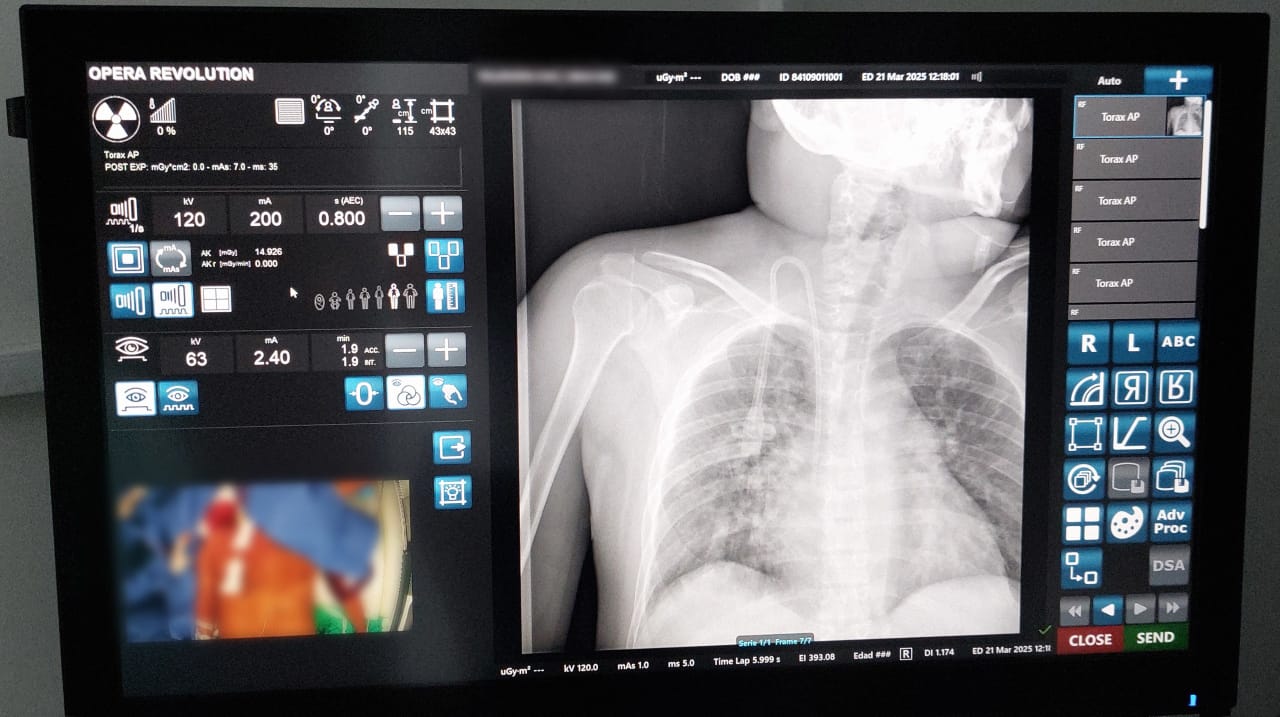

El Instituto Mexicano del Seguro Social (IMSS) en Yucatán informa sobre la reciente adquisición de equipamiento médico, que cuenta con tecnología de punta, se trata del primer fluoroscopio que llegó al Hospital General Regional (HGR) No. 12 “Lic. Benito Juárez”, con el cual se podrán realizar estudios de imagen o rayos X, y al mismo tiempo realizar diversos procedimientos de alta complejidad como cateterismos, a través de la resolución de imágenes en movimiento en tiempo real.

El jefe del Departamento de Rayos X del HGR No. 12, doctor Gabriel Ortega Zumárraga, aseguró que este fluoroscopio es el primero en la representación en Yucatán, se podrán atender diversos padecimientos gracias a que permite visualizar las intervenciones en diversos órganos como el corazón o los pulmones y servir de guía para los procedimientos, así como ayudar a detectar enfermedades u otras anomalías.

“Este tipo de tecnología permite la recopilación de información en tiempo real, lo que da acceso a ver el movimiento y las diferentes posiciones anatómicas en las cuales se encuentra cierto instrumento que requieren los especialistas y, así brindar a las y los derechohabientes mejores resultados para salvaguardar su vida”, aseguró el doctor Ortega Zumárraga.

Tal es el caso de Iesus V, primer derechohabiente intervenido con el fluoroscopio a quien le colocaron un “Catéter Permacath”, el cual es utilizado para el tratamiento de hemodiálisis. A través de esta tecnología, la doctora Elena Solís Montero, del servicio de Angiología del HGR No. 12, colocó quirúrgicamente dicho catéter en el pecho del paciente.

“Poder ver en tiempo real la intervención del paciente, nos permite disminuir cualquier complicación y en este caso, como es un procedimiento endovascular, donde trabajamos las grandes venas del cuerpo, como la yugular o la cava superior, el tener esta tecnología, reducimos significativamente el riesgo de complicaciones en el paciente, quien podrá llevar a cabo su procedimiento de hemodiálisis, con una mayor durabilidad”, enfatizó la especialista.

El titular del IMSS Yucatán, doctor Alonso Juan Sansores Río, aseguró que esta nueva adquisición es resultado de diversas gestiones que traerá grandes beneficios a la población derechohabiente en el estado. Con este fluoroscopio se suman opciones para brindar resultados más certeros en la complejidad de los procedimientos, tales como: angioplastia, colocación de stents o catéteres, cateterismo cardíaco, implantación de marcapasos y desfibriladores, colocación de endoprótesis esofágicas y biliares, inyección de anestesia local o esteroides en articulaciones o nervios específicos, así como biopsias y diversos procedimientos.

Por último, el doctor Gabriel Ortega Zumárraga, manifestó que con este equipamiento de última generación, se brinda la posibilidad a la población derechohabiente que estén imposibilitados para moverse, de adquirir imágenes radiológicas, como resultado de la versatilidad de este fluoroscopio de alta gama y con una alta variedad de opciones de movimiento, que se adapte a las necesidades de las y los pacientes.